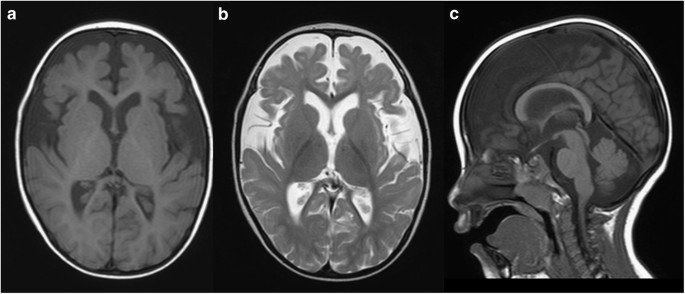

At present, his weight is 9.7 kg (<3rd percentile), length is 83.4 cm (3–10th percentile), and occipito-frontal circumference is 44.5 cm (<3rd percentile), indicating postnatal microcephaly. He exhibits a flat face, hypertelorism, short nose, thin upper lip, and down-turned corner of the mouth. His head is still not controlled. Rolling over has never been achieved. Brain magnetic resonance imaging examination at 2 years revealed cerebral volume loss in association with delayed myelination in the deep white matter (Figure 1).

Brain magnetic resonance imaging examination at 2 years of age. Axial T1- and T2-weighted images (a and b, respectively) and a sagittal T1-weighted image (c). Decreased volume of the cerebrum (a, b) and delayed myelination in the deep white matter (b) are evident. The volume of the corpus callosum is also reduced (c).